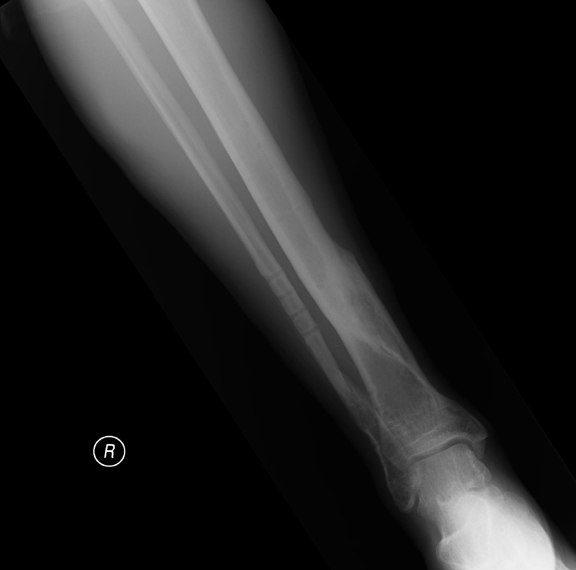

Snapped Fibula